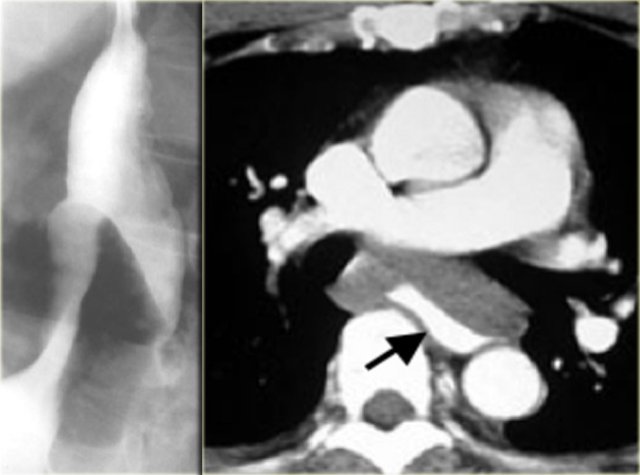

On the left another case of pseudoachalasia.

Distal narrowing simulates achalasia, but narrowing is eccentric, shoulders are asymmetric (arrows), and the mucosa is irregular at the tip of narrowing.

CT shows gastric fundus thickening (arrows) due to adenocarcinoma.